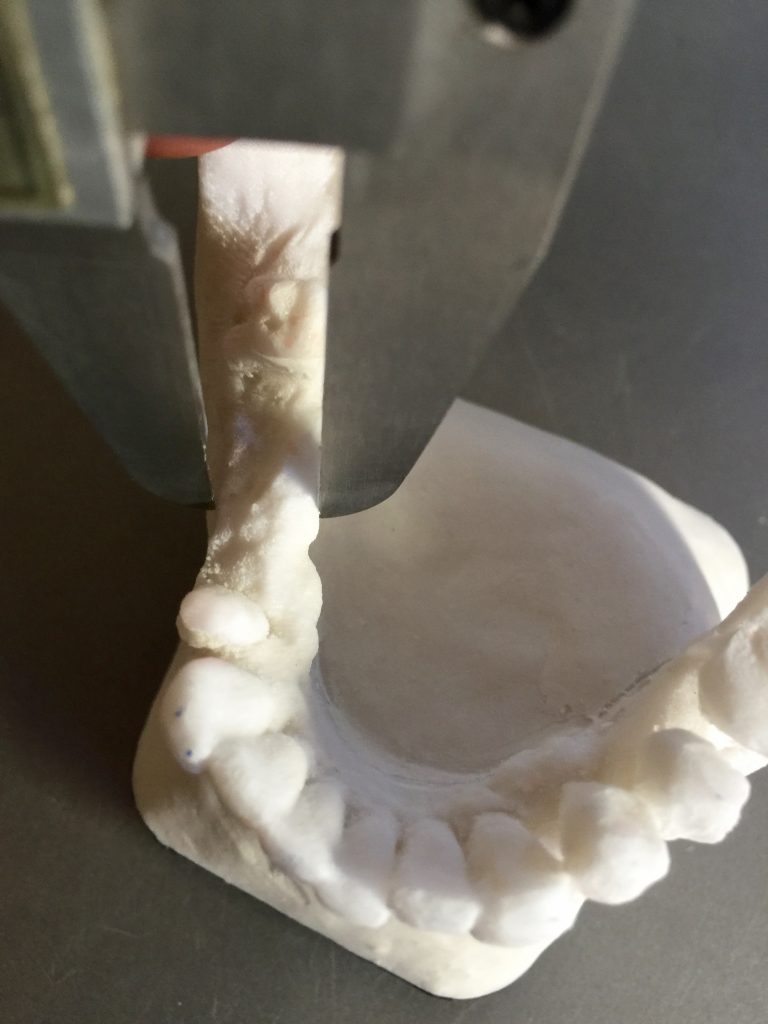

Autores: PRÓLOGO Asimismo, desde el punto de vista pedagógico, el profesional nobel en la materia tiene a su alcance la posibilidad de corregir cualquier posición implantaría en el ordenador, planear los provisionales y plasmarlos en la bio réplica antes de tocar al paciente a operar. Todos estos razonamientos nos llevan a presentar un caso de condiciones muy favorables para poner en práctica estos métodos como primer acercamiento a una Odontología Digital de alta calidad, con medios informáticos, que ya están presentes en la profesión de hoy en día, y será la protagonista única del futuro. Por otro lado, después de numerosos estudios que nos llevan a plantear el “gap” entre implante y pilar(abuttment), como principal responsable de la periimplantitis dado que la microbiota presente en el mismo es imposible de limpiar y en su presencia la cortical ósea reacciona reabsorbiéndose, nos ha llevado a utilizar implantes monobloc ya que los ejes implantarios y protéticos coincidían, y nos permitían su uso. Además, el circonio, ha mostrado a la luz de estudios muy recientes, una preservación y adhesión de los tejidos blandos superiores al titanio, tanto en su tratamiento de superficie de la rosca como a nivel gingival. DESARROLLO Paciente varón de 68 años, con antecedentes de radio/quimioterapia cinco años antes, con Rehabilitación Oral de los cuatro cuadrantes, con una Oclusión Mutuamente Compartida conservada, (REF.8) la que fracasa en el cuadrante 4, 19 años después. El mismo presentaba un puente de porcelana sobre circonio con pilares en 44 y 47, reemplazando el edentulismo de 45 y 46. Se produce la fractura del PM del 44, y ante una endodoncia antigua y corta, se decide implantar las zonas edéntulas, conservando temporariamente los pilares, hasta producida la oseointegración, para entonces también exodonciar el 44. DIAGNÓSTICO Tomamos impresiones del maxilar antagonista, Arco Facial Estático y realizamos montaje del mismo mediante la sistemática ARTEX. Producimos la relajación del músculo Pterigoideo Externo, para obtener la ORC (Oclusión en Relación Céntrica) mediante el método de Laminillas de Long, basado en el concepto de INERVACIÓN RECÍPROCA. Esto nos permitirá montar el maxilar inferior, tanto en su forma de: La primera para practicar la cirugía guiada y comprobar su eficacia, y el modelo de yeso para ser escaneado y confeccionar la GUÍA QUIRÚRGICA. La Biorréplica la obtenemos transformando los archivos DICOM que nos da el CBCT en archivos STL, y a partir de ellos, mediante una tecnología de PROTOTIPADO RÁPIDO, la obtención de un objeto físico en 3D a través de la aglutinación selectiva de una sucesión de capas de polvo. Procedemos a montar la biorrèplica y el modelo de yeso del caso. Podemos verificar la exactitud de las medidas del hueso residual en la bio réplica y compararlas con el scanner. Arrojando un resultado de 8,5 mm de cortical externa a cortical externa. Pudiendo también medir la distancia hasta el dentario. y comparar gracias a la ventana lateral de la biorréplica Dándonos 22mm de distancia. Con lo cual deducimos que implantes de 4,1mm por 12 mm serán perfectamente rodeados de hueso. Medimos también la distancia desde oclusal del antagonista, hasta el hueso desnudo. Lo mismo que, mediante la utilización de la guía radiológica, con un material radiolúcido colocado en gingival de la misma, podemos medir la altura de la encía. Con lo cual podemos calcular la altura del pilar. Es entonces cuando con el programa COC Diagnostix se realiza la programación final: Obteniendo no solo la ubicación, largo, ancho y ángulo de los implantes sino también los provisionales mediante CAD CAM. Ya entonces podemos hacer la práctica quirúrgica en la bio réplica, mediante la guía quirúrgica, instalando los implantes de prueba que no serán los de circonio, ya que la casa no cuenta con ellos, pero si otros de las mismas dimensiones. TRATAMIENTO Entramos ya en la cirugía propiamente dicha. Antisepsia de la zona a operar y zonas anexas. Comprobación del perfecto ajuste e inmovilidad de la G.Q. en boca durante la cirugía. Marcado de la encía y perforación de la cortical. Visión a través de la Guía de la mínima intervención anterior. Comprobación sin Guía. Incisión mínima mesio distal, para apartar y conservar encía queratinizada. Secuencia de drills, perforando a profundidad requerida Observación del Mínimo Trauma Implantes Strauman de Zirconio Monoblock en blíster y montádo en contrángulo reductor. Instalación controlando torque con contrángulo reductor. Comprobación clínica. Comprobación Radiográfica y con Guía. Toma de impresiones, y armado de modelos con técnicas de pasividad protética. Montaje. Resultado de las provisionales ejecutadas por CAD CAM Al no estar conformes con el resultado decidimos desechar dichas provisorias y optar por repetirlas. Nuevas provisorias realizadas mediante encerado convencional. Estado de los tejidos blandos. Provisorias en boca. Oclusión de Estímulo Inmediato. Ref.10: Carga inmediata .Alberto y Diego Bechelli. Comprobación mediante CBCT post operatorio Componentes del equipo (En la próxima presentación, mostraremos las coronas definitivas de porcelana sobre circonio, y la desoclusión provocada por una OCLUSIÓN MUTUAMENTE COMPARTIDA, sobre estos implantes y otros seis mas) REFERENCIAS

FIG: 14-15-16-17-18-19-20

Fig. 14

Fig. 15

Fig. 16

Fig. 17

Fig. 18

Fig. 19

Fig. 20